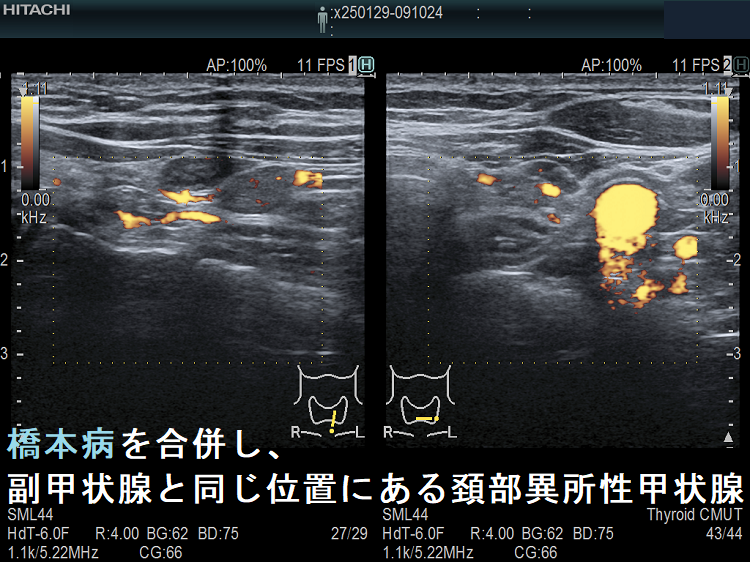

橋本病を合併し、副甲状腺と同じ位置にある頚部異所性甲状腺

橋本病を合併し、下極の副甲状腺と同じ位置にある異所性甲状腺。甲状腺本体と同様の破壊性変化を認めます。

橋本病の異所性甲状腺 超音波(エコー)画像 ドプラーモード

橋本病を合併した頚部異所性甲状腺:下極の副甲状腺と同じ位置にある異所性甲状腺。特徴的な2連構造で、甲状腺本体と同様の破壊性変化を認めます。

橋本病を合併し、副甲状腺と同じ位置にある頚部異所性甲状腺1

橋本病を合併し、副甲状腺と同じ位置にある頚部異所性甲状腺;特徴的な2連構造。甲状腺本体に極めて近い内部構造ですが、やや嚢胞変性が強い印象。癌の転移リンパ節との鑑別が問題になります。

橋本病を合併し、副甲状腺と同じ位置にある頚部異所性甲状腺 ドプラーモード